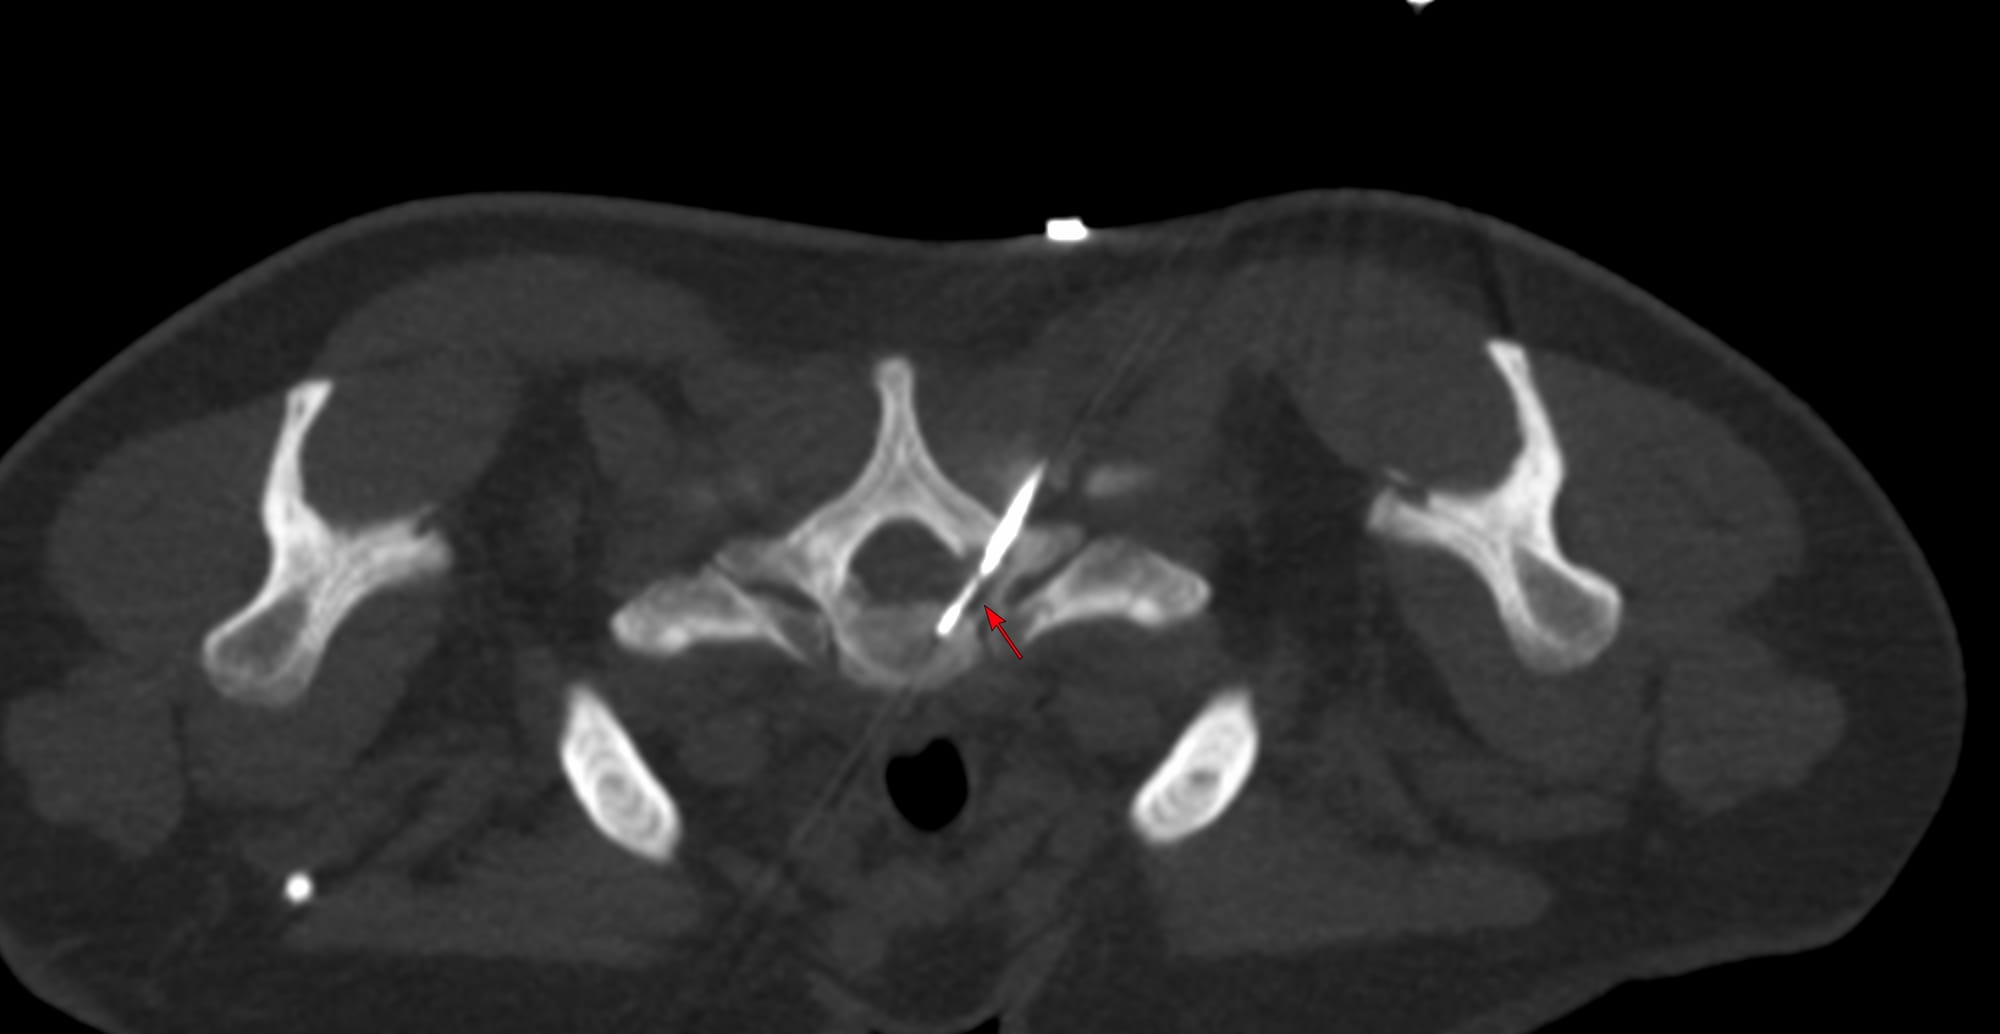

Case of the Day - 098 - 2025 09 08 - Confirming Tuberculosis of the Lower Cervical Spine

Bhavin Jankharia - 09 September 2025